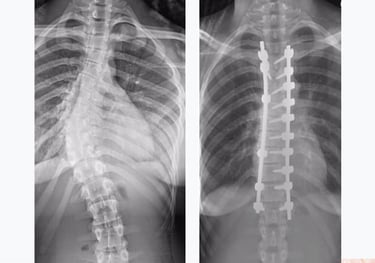

Scoliosis treatment. Chiropractic care for scoliosis should be part of a comprehensive approach to managing the condition, which may also include input from physical therapists, orthopedic surgeons, and other healthcare professionals. The goal is to improve the patient's overall well-being, reduce pain, and enhance spinal function to the best extent possible. Read more